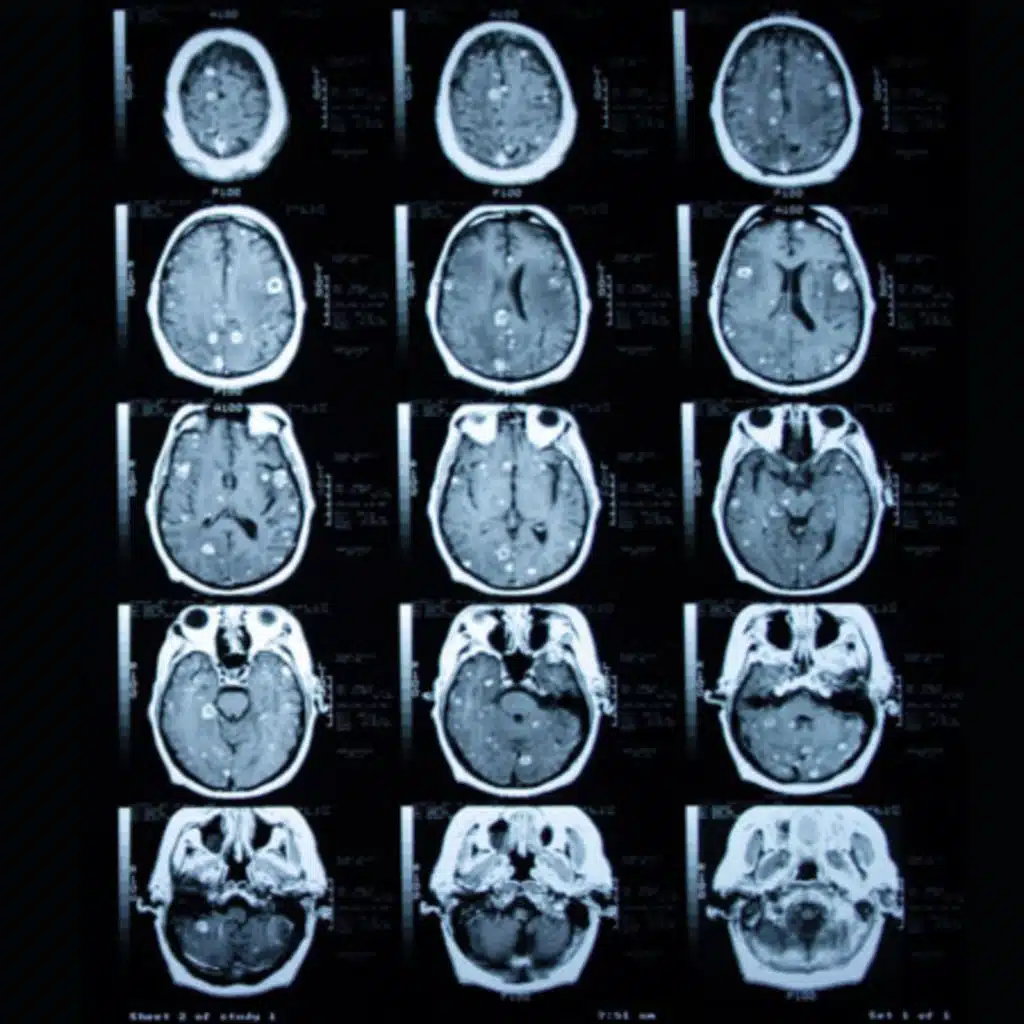

Interview with David R. Raleigh, MD, PhD, and William C. Chen, MD, authors of Efficacy and Safety of Stereotactic Radiosurgery for Brainstem Metastases: A Systematic Review and Meta-analysis